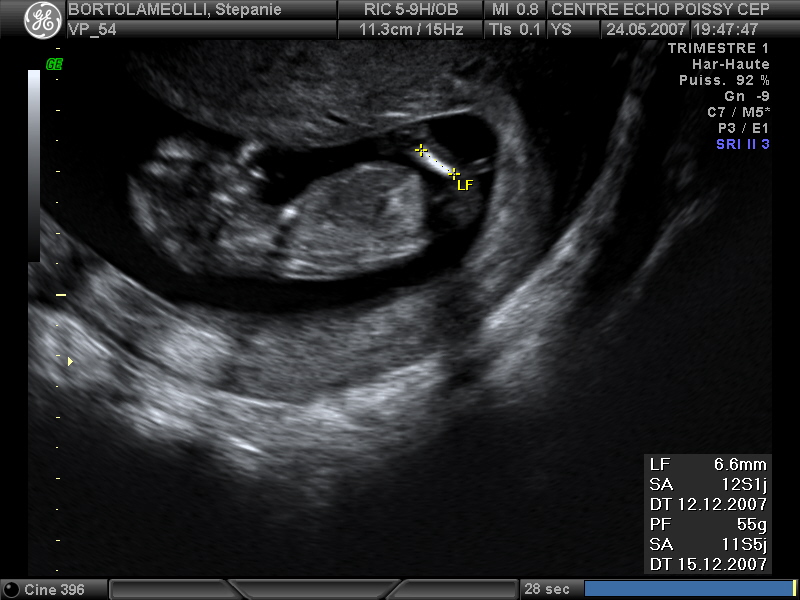

Echographies

Mai 2007